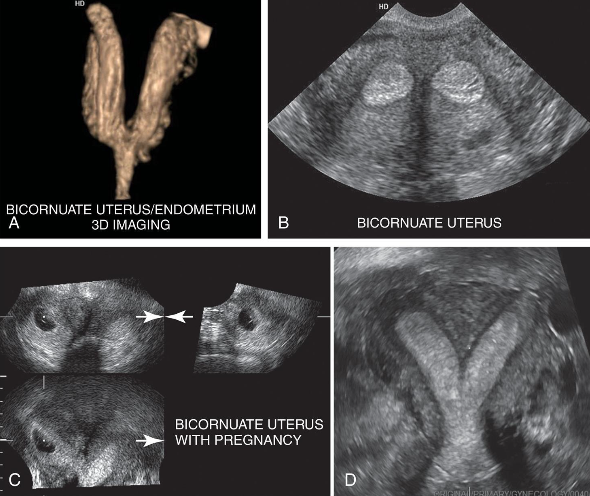

– Improper fusion leads to two partially or completely separate bicornuate uterine cavities.

– The uterus is heart-shaped

– Most common congenital uterine anomaly.

Bicornuate uterus

This is?

Bicornuate Uterus